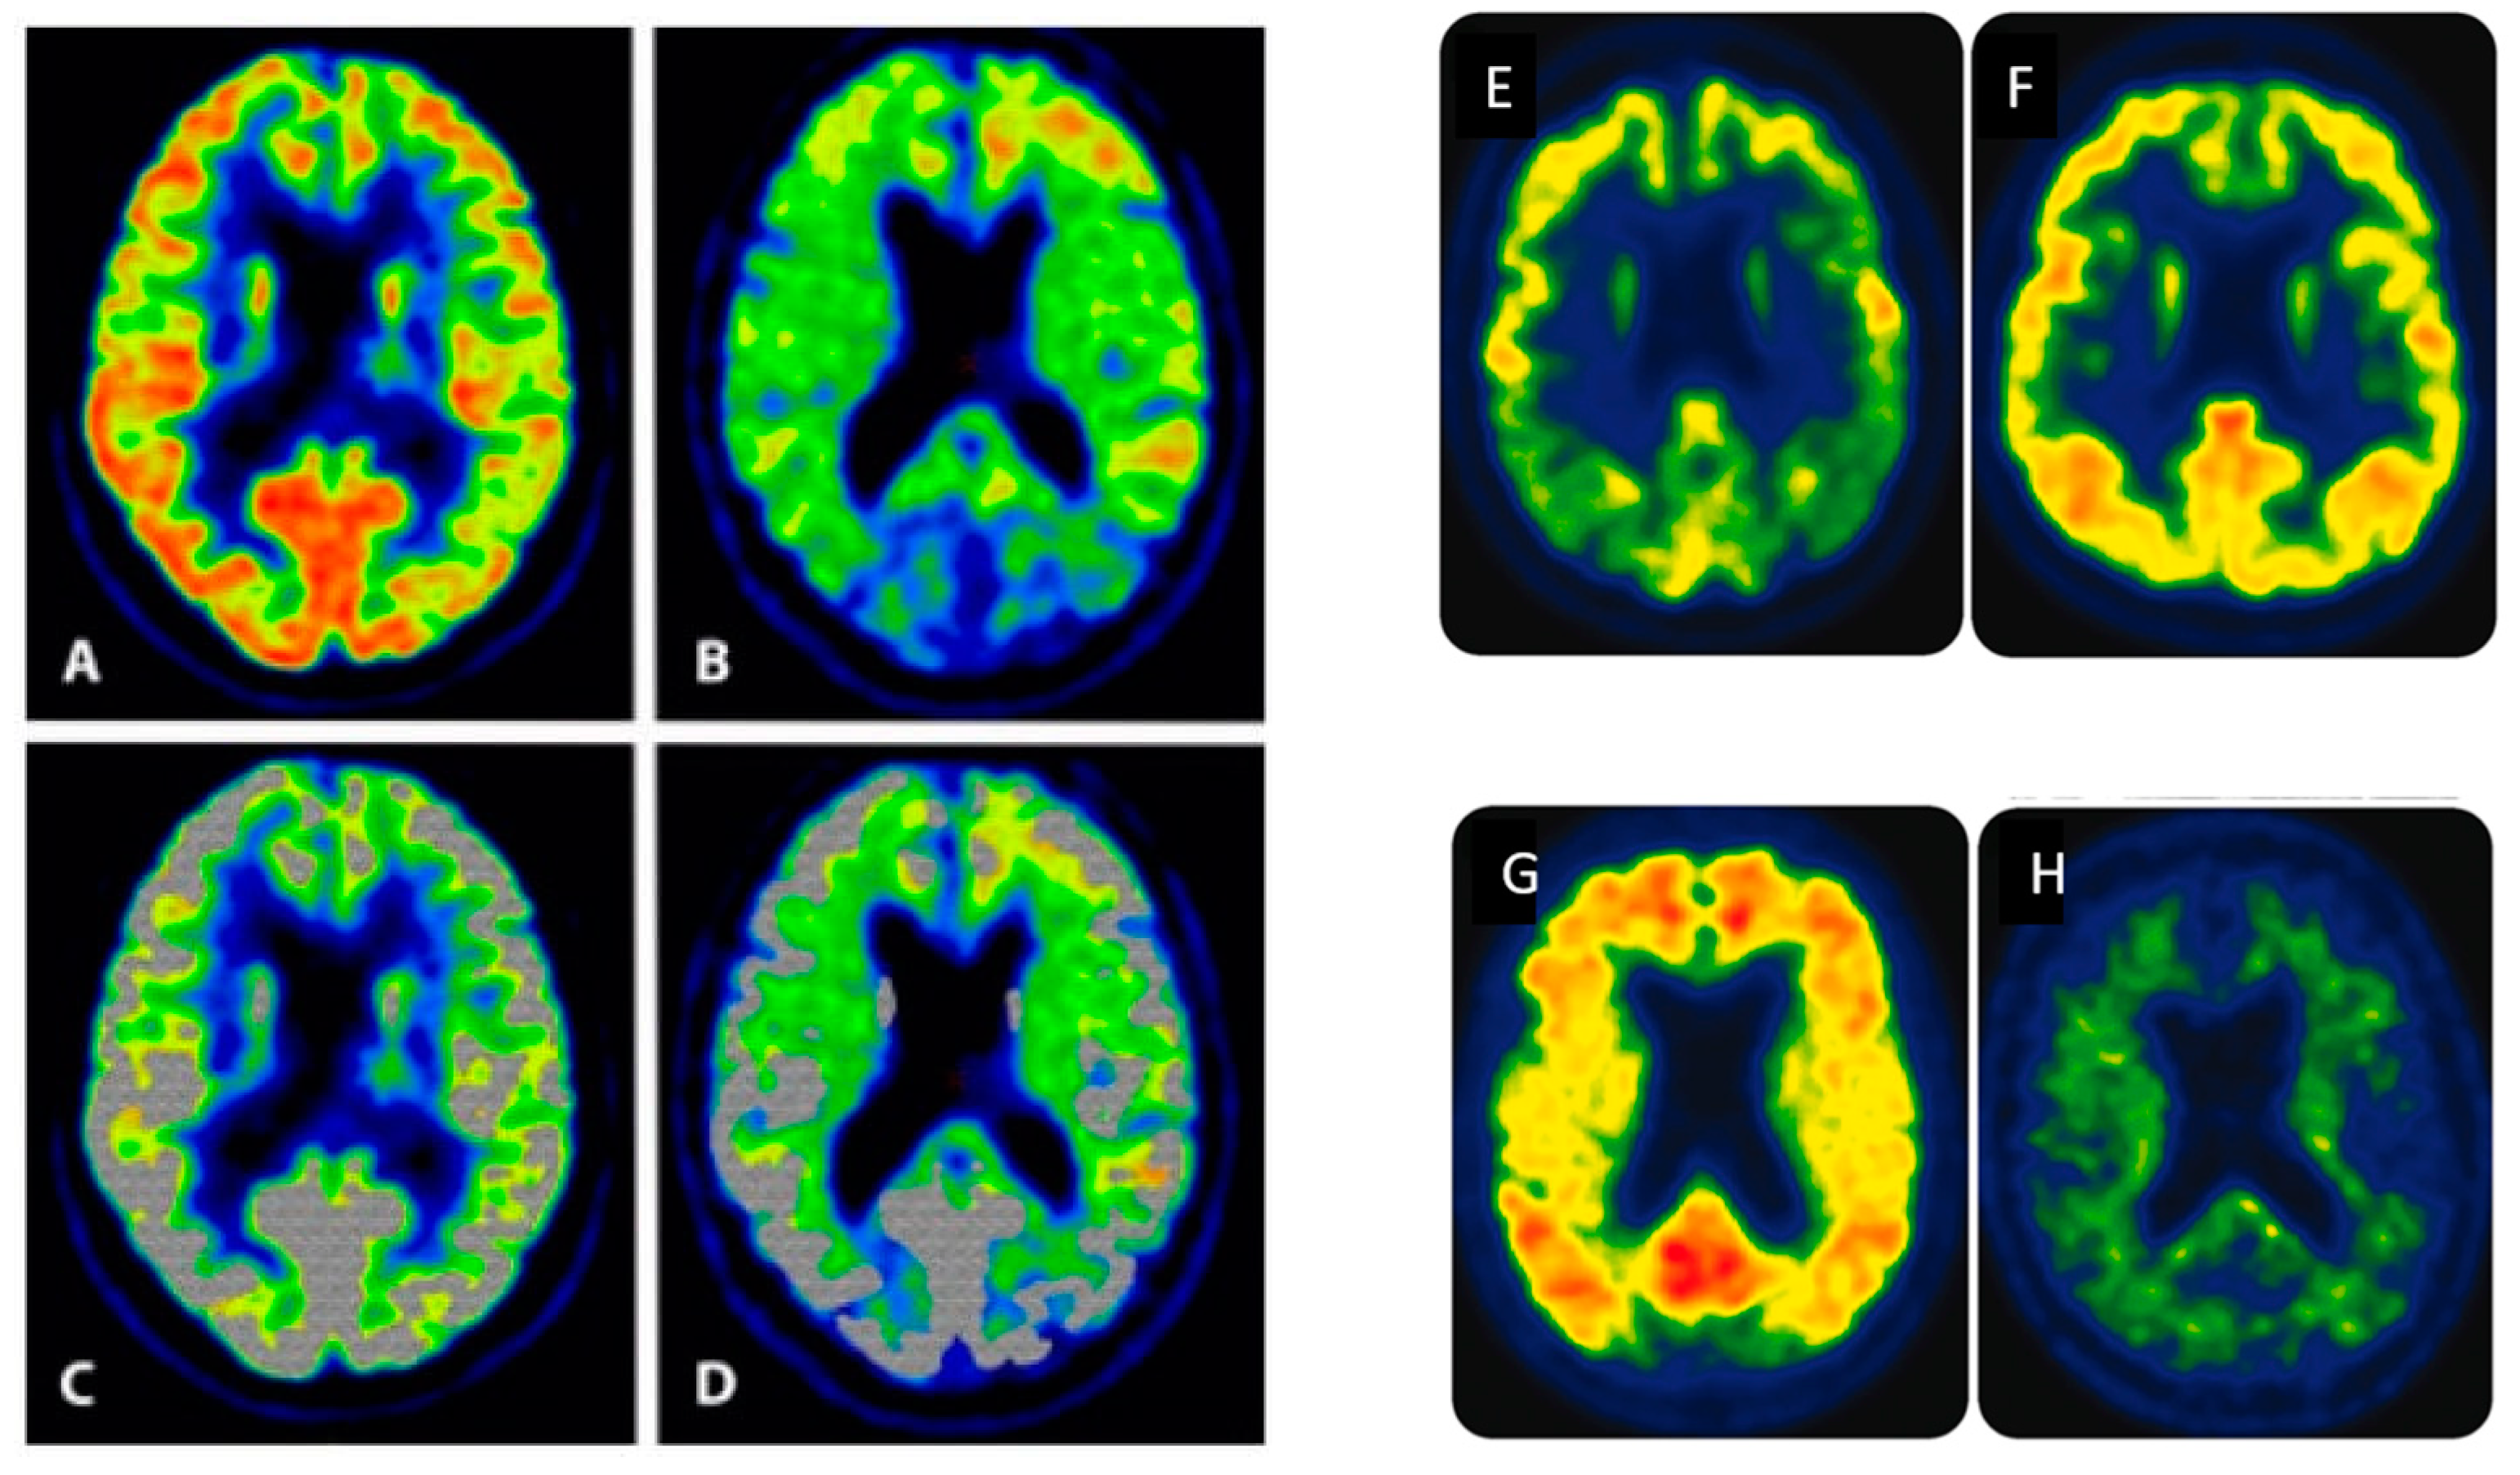

- Høilund-Carlsen, P.F.; Revheim, M.E.; Costa, T.; Kepp, K.P.; Castellani, R.J.; Perry, G.; Alavi, A.; Barrio, J.R. FDG-PET versus Amyloid-PET Imaging for Diagnosis and Response Evaluation in Alzheimer’s Disease: Benefits and Pitfalls. Diagnostics 2023, 13, 2254. [Google Scholar] [CrossRef] [PubMed]